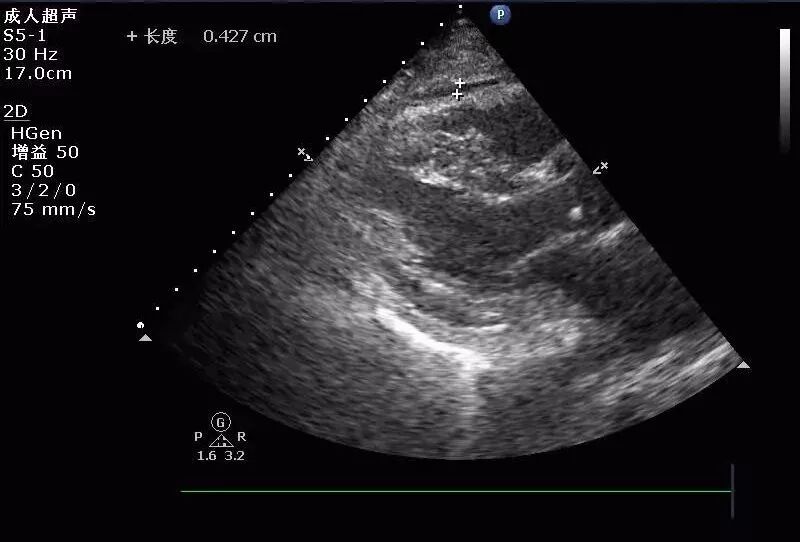

(图7)

(图8)

图7-8  2017年9月6日超声图像

(图9)

(图10)

图9-10  2017年9月13日超声图像